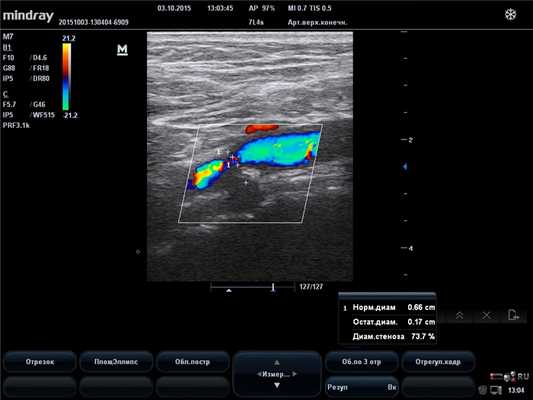

Начальная диагностика для выявления поражения позвоночной артерии на шее проводится с помощью УЗИ с цветовым допплеровским картированием. Ультразвуковое исследование позволяет выявить патологию сосудов у большинства пациентов, однако этот метод зависит от используемой аппаратуры и навыков врача УЗИ. Метод позволяет выявить сужение в шейном отделе позвоночной артерии, структуру атеросклеротической бляшки, характер кровотока по позвоночной артерии. Транскраниальная допплерография (ТКД) применяется для обнаружения внутричерепного стеноза позвоночной артерии. Метод позволяет в 80% случаев выявить нарушение кровотока в базилярной и позвоночных артериях, возможно исследование с детекцией эмболии (переноса кусочков бляшки в мозговые сосуды), что доказывает роль сужения в развитии нарушений мозгового кровообращения.